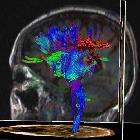

Magnetic

Resonace Imaging findings in a case of infantile Refsum disease. 3D sagittal presentation of fibres confirms reduction of the blue fibres in the rolandic areas and posterior corona radiata, arrangement of the fibere is relatively conserved in the anterior tracts.